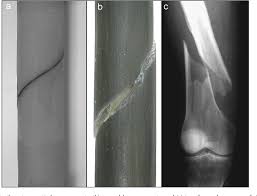

Reconstruction Individual Three Dimensional Model Of Fractured Long Bone Based On Feature Points Springerlink

Reconstruction Individual Three Dimensional Model Of Fractured Long Bone Based On Feature Points Springerlink from media.springernature.com